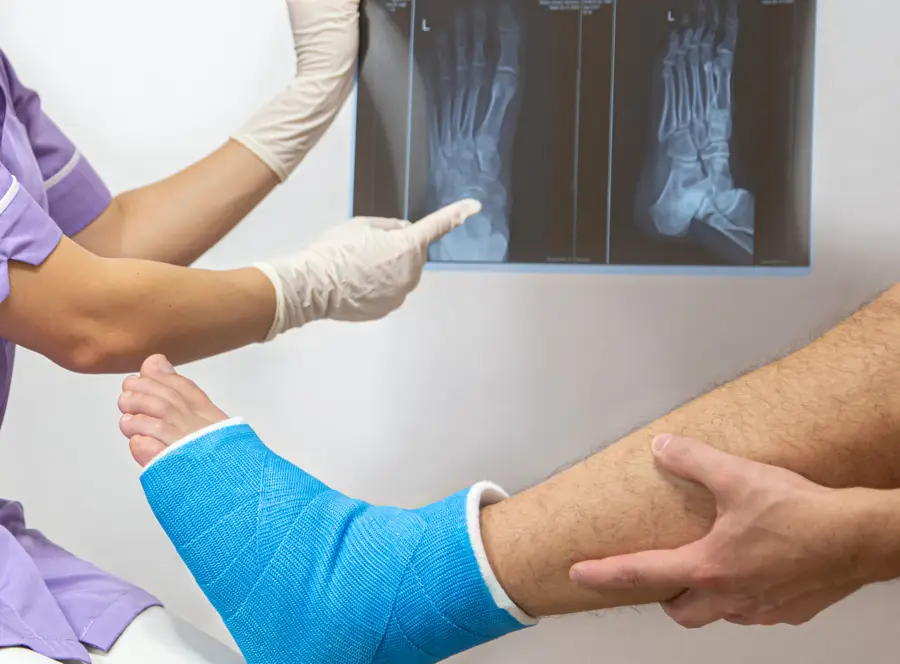

If you suspect a foot or ankle fracture or have any concerns about your lower extremities, we encourage you to schedule an appointment at Northern Ankle Foot Associates. Dr. Joseph is here to provide compassionate care and guide you toward a healthier, pain-free future.